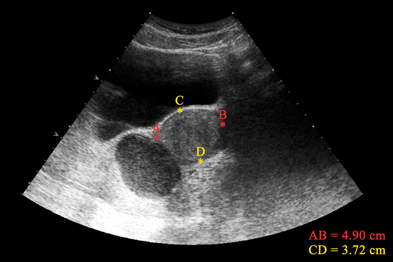

Sonovaginography| Endometriosis Ultrasound | Severe ...

Sonovaginography| Endometriosis Ultrasound | Severe ... from pogu.com.au